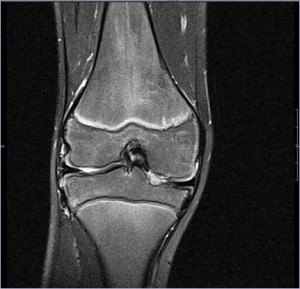

Псориатический артроз диагностируется на основе клинических заболеваний, в основном это псориаз, воспалительные виды артрита и т.п. Одним из первых действий должно быть рентгеновское обследование на наличие повреждений суставов. Для более подробного изучения суставов используют процедуры, такие как МРТ (магнитно-резонансная томография), УЗИ (ультразвуковое исследование), КТ (компьютерная томография).

Диагностика псориатического артрита обычно включает медицинский осмотр, анализы крови для исключения других заболеваний и, возможно, рентгенографию или МРТ для оценки состояния суставов. Врач может также учитывать историю болезни пациента и наличие псориаза для постановки диагноза.